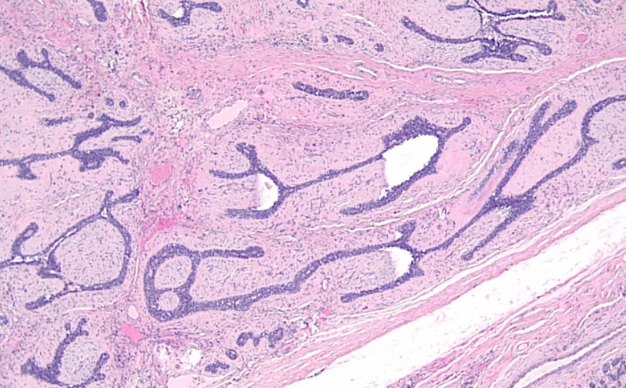

A 30 year old woman presents with a well-circumscribed, mobile, marble-like mass in her right breast. She says that it has grown since her last pregnancy. Biopsy is shown below. What is the most likely diagnosis? What is her prognosis?

Fibroadenoma. Note the fibrous tissue and glands sharply demarcated from adjacent breast tissue. These are the most common tumor in premenopausal women, is benign and is estrogen sensitive. Note that there is no increased risk for breast cancer.